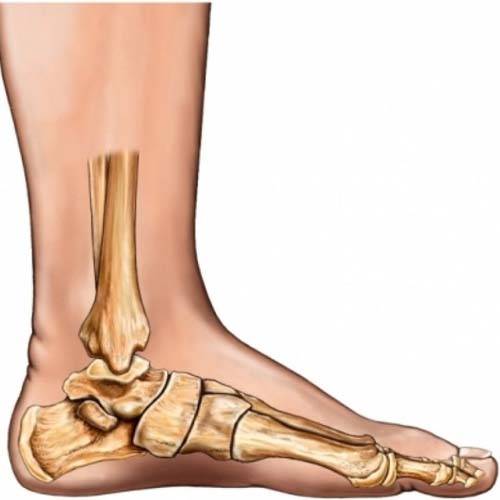

Flat feet, also referred to as flatfoot, is a condition in which one or both feet have little to no arch. When you stand, your foot pads press into the ground. In other words, it is a condition in which the entire foot from the sole to the ball of the feet touches the ground. Typically, there is no visible arch in the foot, though the arch can be seen when the foot is lifted.

A very common condition, Flat Foot or Pes Planus or fallen arches is found in about 30% of the general population. An absence or reduction of the arch, which is often found between the heel and the ball of the foot, is indicative of a flat foot. Normally, both feet are affected, but a fallen arch on only one foot is possible. A variety of conditions, including injuries, obesity, and arthritis, can result in flat feet. Flat feet can also be caused by aging, genetics, and pregnancy. You are also more likely to have flat feet if you have a neurological or muscular disease like cerebral palsy, muscular dystrophy, or spina bifida. Flat feet must be properly cared for because they can cause pain, stress, and imbalances in other parts of your body. Your entire body can be aligned by making an effort to reduce flatness. This might help with various bodily problems that flat feet can bring.

Flat feet can be divided into two categories: flexible flat feet and rigid flat feet. When the leg is not being supported by the ground, the arch of a flexible flat foot is evident; however, when the individual is standing, the arch disappears. In a rigid flat foot, there is no arch at all.